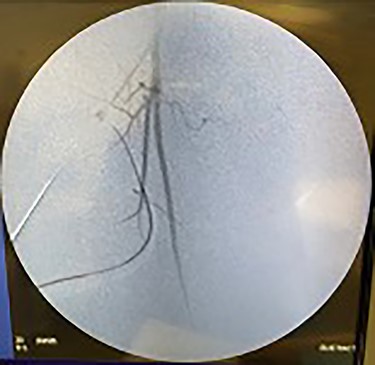

Catheter arteriogram results showed significant occlusion of the left iliac artery (Figs 3 and 4), the right iliac artery (Fig. 1), as well as the distal abdominal aorta (Fig. 2). There were numerous collateral vessels noted, indicating the presence of long-standing proximal stenosis (Fig. 1). The decision was made to use angioplasty to help widen the areas of stenosis. An 8 mm × 40 mm Passeo balloon was advanced from the right femoral artery into the left iliac artery (Fig. 7) and insufflated to 6 mmHg (Fig. 6). The balloon was allowed to remain expanded for 1 min and then was deflated. Next, the distal aorta was repaired in a similar fashion. The balloon was advanced into the distal aorta from the right femoral access and insufflated to 12 mmHg (Fig. 8). The balloon was allowed to remain expanded for 90 s.

Lastly, the right iliac artery (Fig. 5) was treated using the same method (Fig. 10). After completion of the angioplasty procedure, catheter arteriogram was repeated to visualize the effectiveness of the procedure in relieving the extensive stenosis. The imaging revealed almost complete restoration of the diameter of both left and right iliac arteries (Figs 11 and 12). The distal aorta also showed improved diameter after the procedure (Fig. 9). Angiogram of both lower extremities was also performed. The catheter was passed distal to the stenosis that was previously present in the left iliac artery, to help visualize perfusion of its distal branches (Figs 13 and 14). The catheter was removed from the right femoral artery and reinserted in a distal fashion, to help visualize downstream perfusion. The right popliteal artery was well visualized on angiogram (Fig. 15), signifying strong perfusion. The patient was strongly advised to discontinue smoking cigarettes. In addition, the patient was advised to maintain regular physical exercise as tolerated and take baby aspirin daily to prevent thrombotic events.